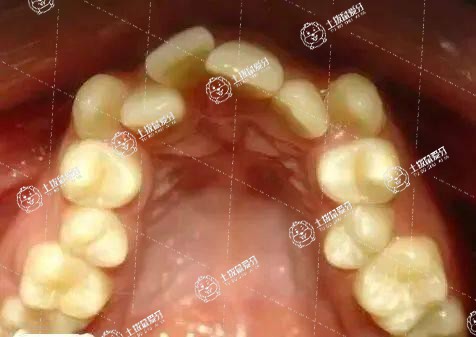

有矯正牙齒需求的小伙伴或許都聽過(guò)骨性牙齒矯正,骨性牙齒矯正的難度相對(duì)來(lái)說(shuō)比較大,因此,在效果上可能需要一點(diǎn)時(shí)間,骨性牙齒矯正有效果嗎 ?牙科醫(yī)生負(fù)責(zé)任的告訴大家,肯定是有效果的,不過(guò)具體的效果會(huì)根據(jù)牙友自身的年齡以及具體的難度來(lái)決定。

牙齒骨性反頜戴矯正器肯定是有效的,但是根據(jù)不同的年齡和不同的嚴(yán)重程度效果會(huì)有所差別。

反頜在乳牙期可能就有所體現(xiàn),這是個(gè)時(shí)候往往表現(xiàn)為單純牙齒的反頜,最佳矯治時(shí)期是3~5歲,早期糾正咬合關(guān)系,可以使恒牙發(fā)生反